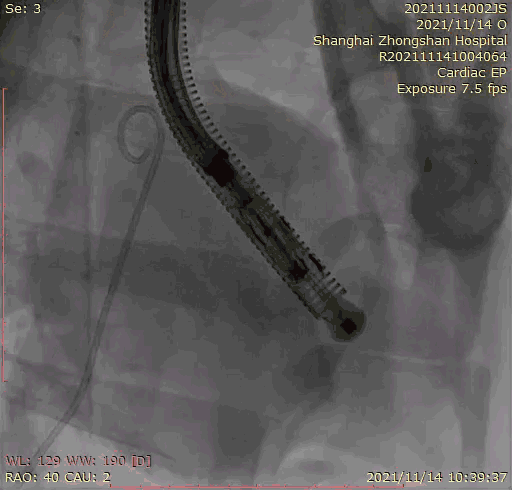

本次臨床前研究經(jīng)右側(cè)頸靜脈置入LuX-Valve Plus輸送系統(tǒng)可調(diào)彎鞘管,在DSA及超聲引導(dǎo)下將人工三尖瓣瓣膜植入到原有三尖瓣位置,利用獨特的錨定技術(shù)將人工瓣膜支架可靠固定在預(yù)定的位置。